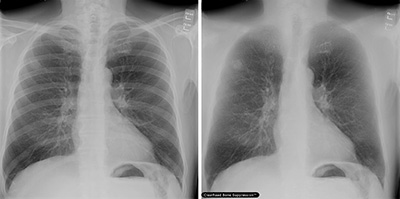

「胸部X線骨組織透過ソリューション」コーナー

昨年発表し好評を博した胸部X線骨組織透過ソリューション“ClearRead BS”は胸部X線画像の骨組織透過処理により,通常の撮影で得られた1枚の元画像から骨組織透過画像を生成,肺組織における結節や異常陰影の視認性を向上させ,医師の読影を強力に支援します。今年は新たにClearRead BSに追加搭載する2つの新しい画像処理技術である胸部X線経時差分ソリューション” ClearRead +Compare”および胸部X線医療用チューブ強調ソリューション“ClearRead +Comfirm”を展示します。さらに進化した他に類を見ない最先端の画像処理技術を紹介します。

展示製品

・胸部X線骨組織透過ソリューション“ClearRead BS”

・胸部X線経時差分ソリューション” ClearRead +Compare”

・胸部X線医療用チューブ強調ソリューション“ClearRead +Comfirm”